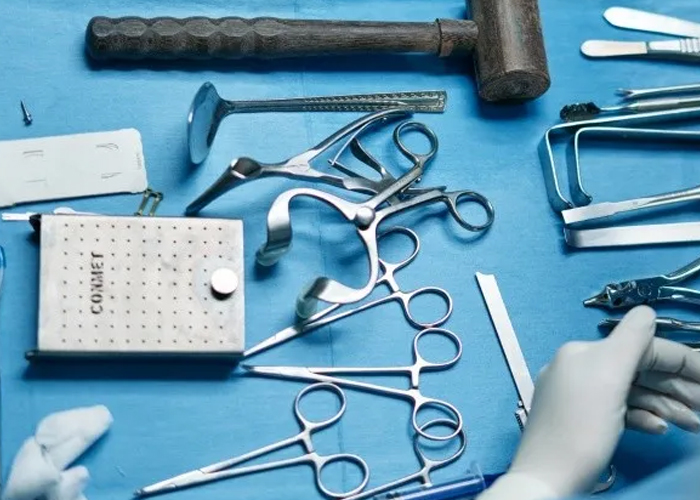

En su lucha por extraer la pelota de golf, los médicos utilizaron seis herramientas distintas, pero con ninguna obtuvieron éxito. Ante ello, al día siguiente le administraron una gran cantidad de laxantes. Afortunadamente, tres horas después el menor logró tener la evacuación exitosa sin evidencia de lesión intestinal.